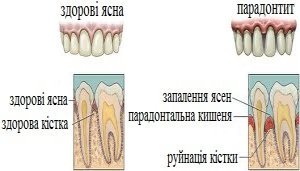

Що таке пародонтоз?

Пародонтоз - це ураження кісткової тканини навколо зуба, яке супроводжується її зменшенням, за відсутності ознак запалення. Дехто помилково вважає, що пародонтоз - це ускладнення пародонтиту. Але це не так, спільним для цих захворювань є лише локалізація, а саме пародонт, комплекс тканин, що оточує та утримує зуб.

При пародонтозі відсутні ознаки запалення: ясна зберігають нормальний вигляд та не кровоточать. Найпоширенішим симптомом, що може свідчити про захворювання є оголення коренів зубів, що супроводжується ниттям.

- Корені зуба оголюються(ретракція);

- Виникає пародонтальна кишеня, куди потрапляють залишки їжі;